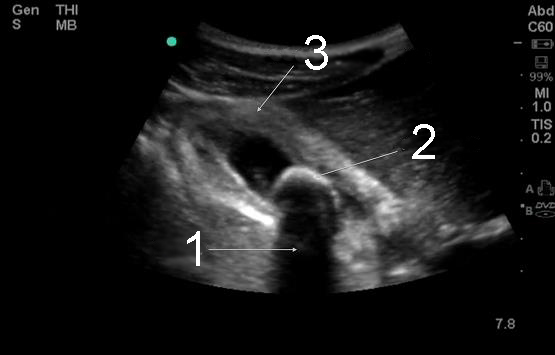

Bild, Gallenblase, transversal, akute Cholezystitis

1. Schallschatten

2. Cholelithiasis

3. Verdickte Gallenblasenwand